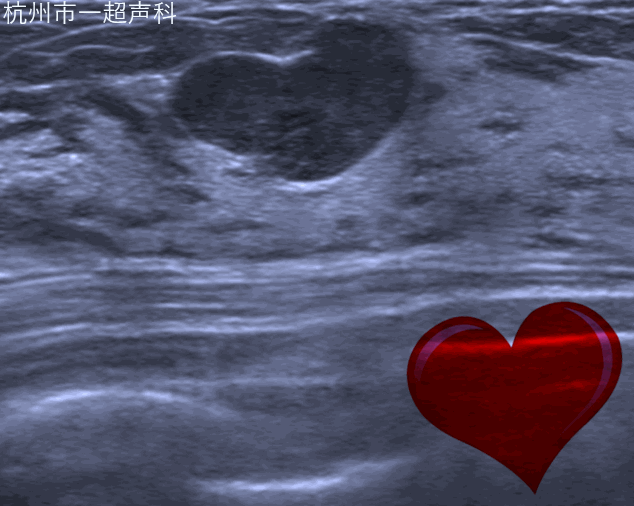

我院超声科开展乳腺超声多模态诊断,包括自动乳腺容积超声、弹性成像、超声造影以及乳腺结节融合成像虚拟导航。

自动乳腺容积超声应用宽幅高频探头的自动扫描实现乳腺全容积的规范化图像,减少漏诊;独特的冠状面对鉴别诊断提供了三维的信息。自动乳腺容积超声对早期乳腺癌的影像学诊断,乳腺结节的BI-RADS分类评估,乳腺肿瘤的临床分期,新辅助化疗的疗效评估,乳腺癌的筛查有明显的优势。超声影像科于2010年在省内率先开展该项技术,也是国内最先开展的蜜桃直播 之一。目前无论在累积的病例数还是诊断水平均属国内领先。2018年,我们完成30000例病人的基础上在国内发布首个自动乳腺全容积成像系统操作流程,为行业制订检查规范。团队发表包括SCI在内蜜桃直播相关的文章40余篇,在RSNA及WFUMB等国际会议发表研究结果,开展全国的多中心研究,与知名院校的产学研合作。每年举办国际级继续教育学习班,作为培训基地,为全国各大蜜桃直播 培训医生200余人。加强国际交流,每年接待来自欧美、亚太地区的专家进行学术交流与合作。